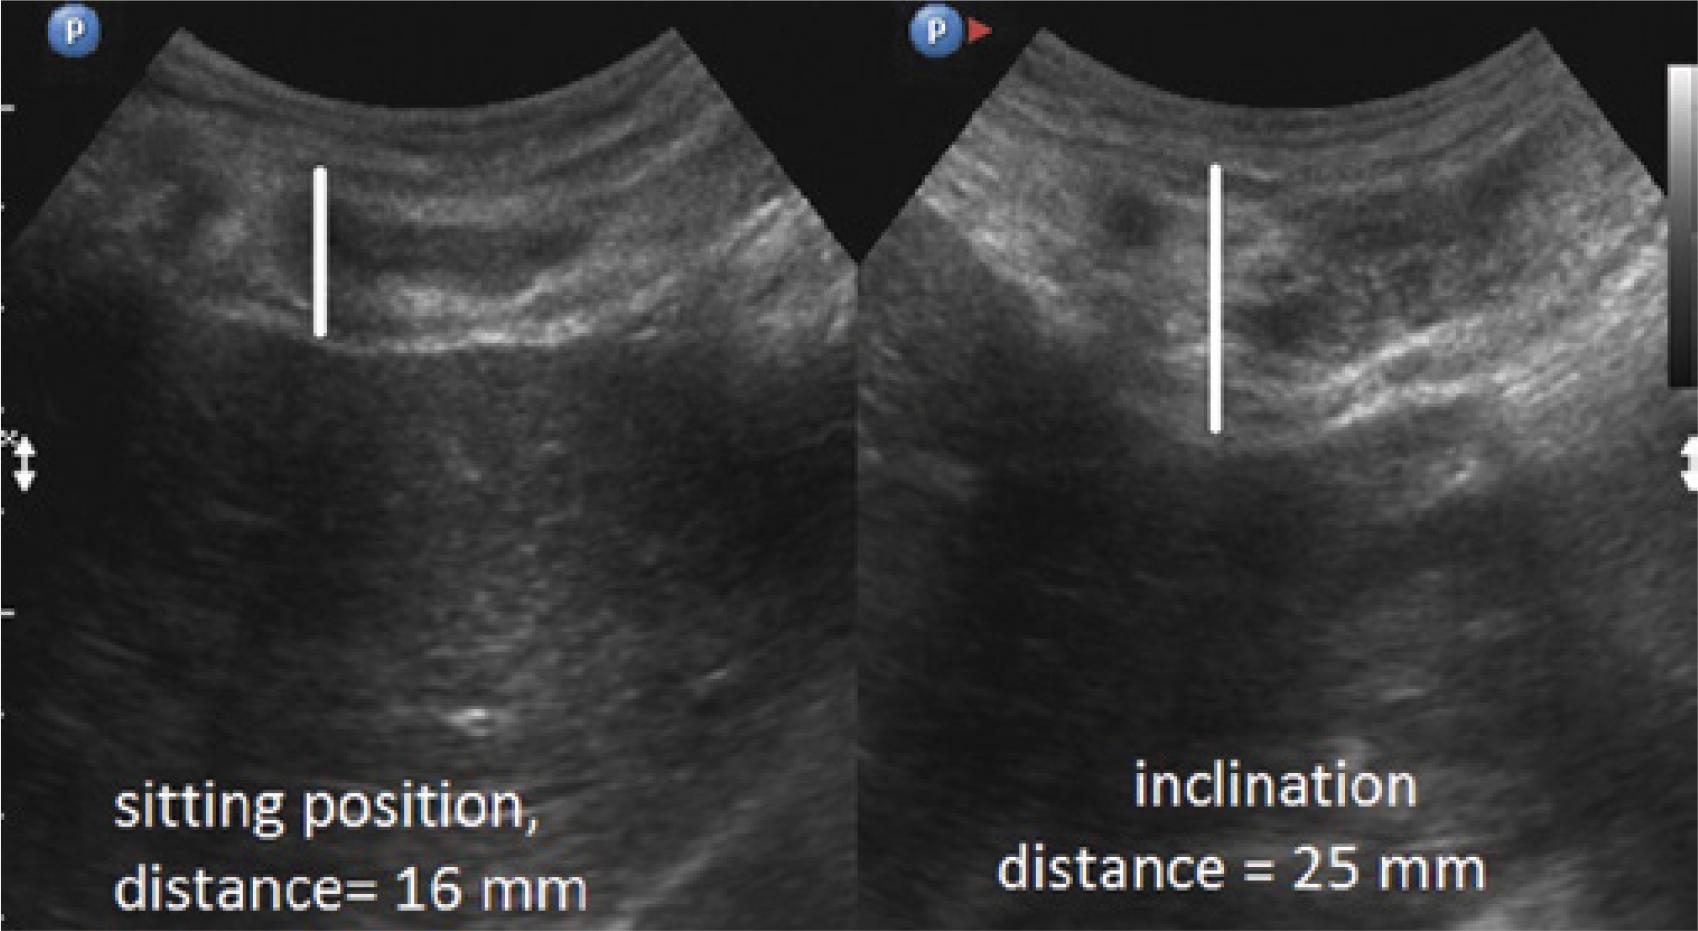

Comparison of the thickness of the musculocartilaginous complex during inhalation, exhalation, supine position, sitting position and forward trunk flexion in 178 patients

| Inhalation | 11–28 mm | 14.5 mm +/− 2.4 | Exhalation | 12–40 mm | 21.5 mm +/− 3.3 |

| Sitting | 11–31 mm | 17.0 mm +/− 2.9 | Flexion | 20–40 mm | 25.4 mm +/− 3.5 |